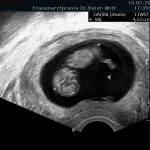

Frühschwangerschaft:

Ultraschall_17